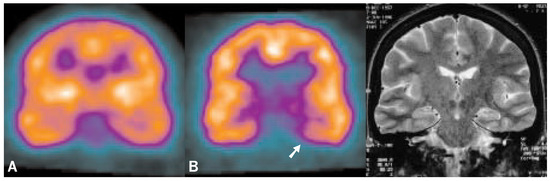

Assessment of the benzodiazepine receptors with SPECT in patients with mesial temporal lobe epilepsy

The goal of epilepsy surgery is to excise the epileptogenic focus or to interrupt propagation of epileptiform activity. The prerequisite for the neurosurgical procedure is the exact localization of the epileptogenic focus in order to avoid postoperative morbidity. PET studies with 11C-Flumazenil have shown the involvement of the benzodiazepine receptors (BDR) in epilepsy. The aim of this study was to examine the clinical value of 123Iodine-Iomazenil (a derivate of Flumazenil) SPECT in relation to interictal rCBF SPECT, EEG and MRI findings in patients with therapyresistant mesial temporal lobe epilepsy, candidates for epilepsy surgery. The results show that 123IIomazenil SPECT for the examination of the benzodiazepine receptors is a sensitive method for the preoperative localization of the epileptogenic focus: the results show a clearly higher sensitivity (89%, similar to ictal CBF SPECT) in comparison to the interictal CBF SPECT (25%). With a positive predictive value of 100%, 123IIomazenil SPECT allows a reliable localization of epileptogenic foci. Since an ictal CBF SPECT is rarely possible due to logistic reasons and due to high sensitivity of the 123I-Iomazenil SPECT, this method has become a routine examination during the intensive preoperative monitoring period. Full article

Figure 1